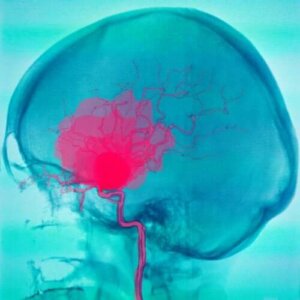

Subaraknoid ve Subdural Kanamalar

Subaraknoid Kanamalar

Subaraknoid kanamalar, araknoid ve pia mater arasında kan havuzlarının bulunduğu yerdir. Kan genellikle arterlerden gelir ve birçok farklı nedeni olabilir. En yaygın olanı bir anevrizmanın rüptürüdür. Ancak, başka nedenleri de olabilir.